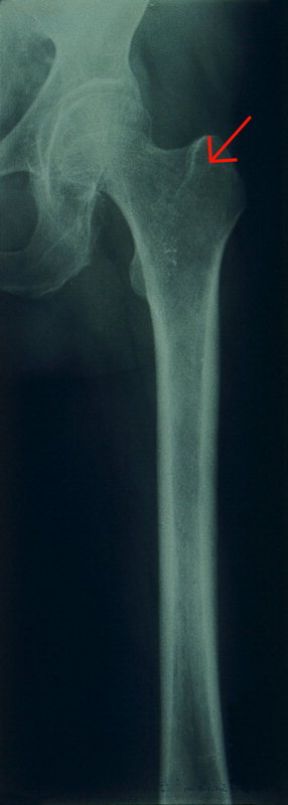

L'osteoporosi, che in maniera massiccia colpisce la popolazione femminile, è un'alterazione degenerativa delle ossa, caratterizzata da una diminuzione del tessuto osseo. Tale patologia può essere associata a diverse malattie, disturbi ormonali, carenze alimentari, forme ereditarie, e all'assunzione cronica di alcuni farmaci. Le donne, come si è detto, vengono colpite più precocemente a causa degli squilibri ormonali derivanti dalla menopausa. Il comparire di sintomi di dolore alla colonna vertebrale è legato alla presenza di microfratture, che possono portare al crollo dei corpi vertebrali. Negli stadi più avanzati della malattia, può addirittura accadere che sia sufficiente sollevare male un peso o inciampare mentre si cammina per provocare la frattura del collo del femore. La terapia, che però non è in grado di curare l'osteoporosi, ma solo di rallentarne il processo, si basa sulla somministrazione di calcio.

L'osteoporosi. Femore. L'osteoporosi è una delle patologie che più frequentemente affliggono le persone anziane. Purtroppo la fragilità ossea può comportare gravi conseguenze come la rottura del femore, in caso di caduta. La freccia indica una zona di rarefazione della densità calcica.